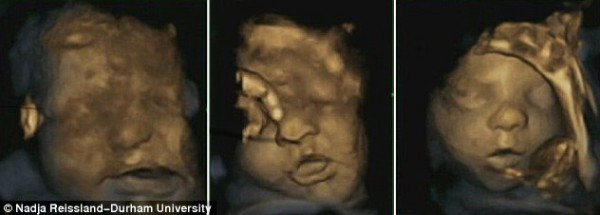

كشف فريق من العلماء والباحثين بجامعة درهام البريطانية عن مفاجأة كبيرة هى الأولى من نوعها على الإطلاق، حيث أشاروا أن الجنين يتمرن على الابتسامة داخل رحم أمه استعداداً للقاء أبويه، وذلك حسبما أظهرت مجموعة من الصور رباعية الأبعاد “4D”، والتى سلطت الضوء على تعبيرات وجوه مجموعة الأجنة قبل حدوث الولادة بفترات تصل إلى 16 أسبوعا.

وعلق علماء النفس بجامعة درهام البريطانية على تلك الصور غير المسبوقة، مشيرين أن الأجنة تتدرب وتمارس كيفية التعبير عن مشاعرها، وخاصة أنهم على موعد قريب للقاء الأب والأم عقب الولادة مباشرة، وأثبتوا أن قدرات الطفل العقلية على إظهار عواطفه ومشاعره تتطور فى وقت مبكر جداً من حياته، وهو ما يعد أمراً مثيراً للغاية.

يذكر أنه تم التقاط هذه الصور رباعية الأبعاد باستخدام أشعة الموجات فوق الصوتية لحوالى 15 جنينا، تتراوح أعمارهم ما بين 24 إلى 36 أسبوعاً من بداية الحمل.